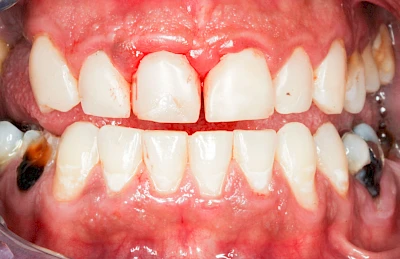

Bakterien in den Zahnbelägen greifen neben den Zähnen auch das Zahnfleisch (Gingiva) und den gesamten Zahnhalteapparat (Parodont) an. Der Körper reagiert mit einer Entzündung, sichtbar als Rötung und Schwellung. Meist blutet das Zahnfleisch z .B. beim Essen oder auch beim Putzen der Zähne.

Ist zunächst nur das Zahnfleisch von der Entzündung betroffen, spricht man von Gingivitis. Später, wenn auch der Knochen um die Zähne herum entzündet ist, spricht man von einer Parodontitis. Bei der Parodontitis wird der Knochen nach und nach abgebaut und das Zahnfleisch zieht sich zurück. Die Zahnhälse und Zahnwurzeloberflächen liegen mehr und mehr frei. Die Zähne werden zunehmend lockerer und fallen schließlich aus.